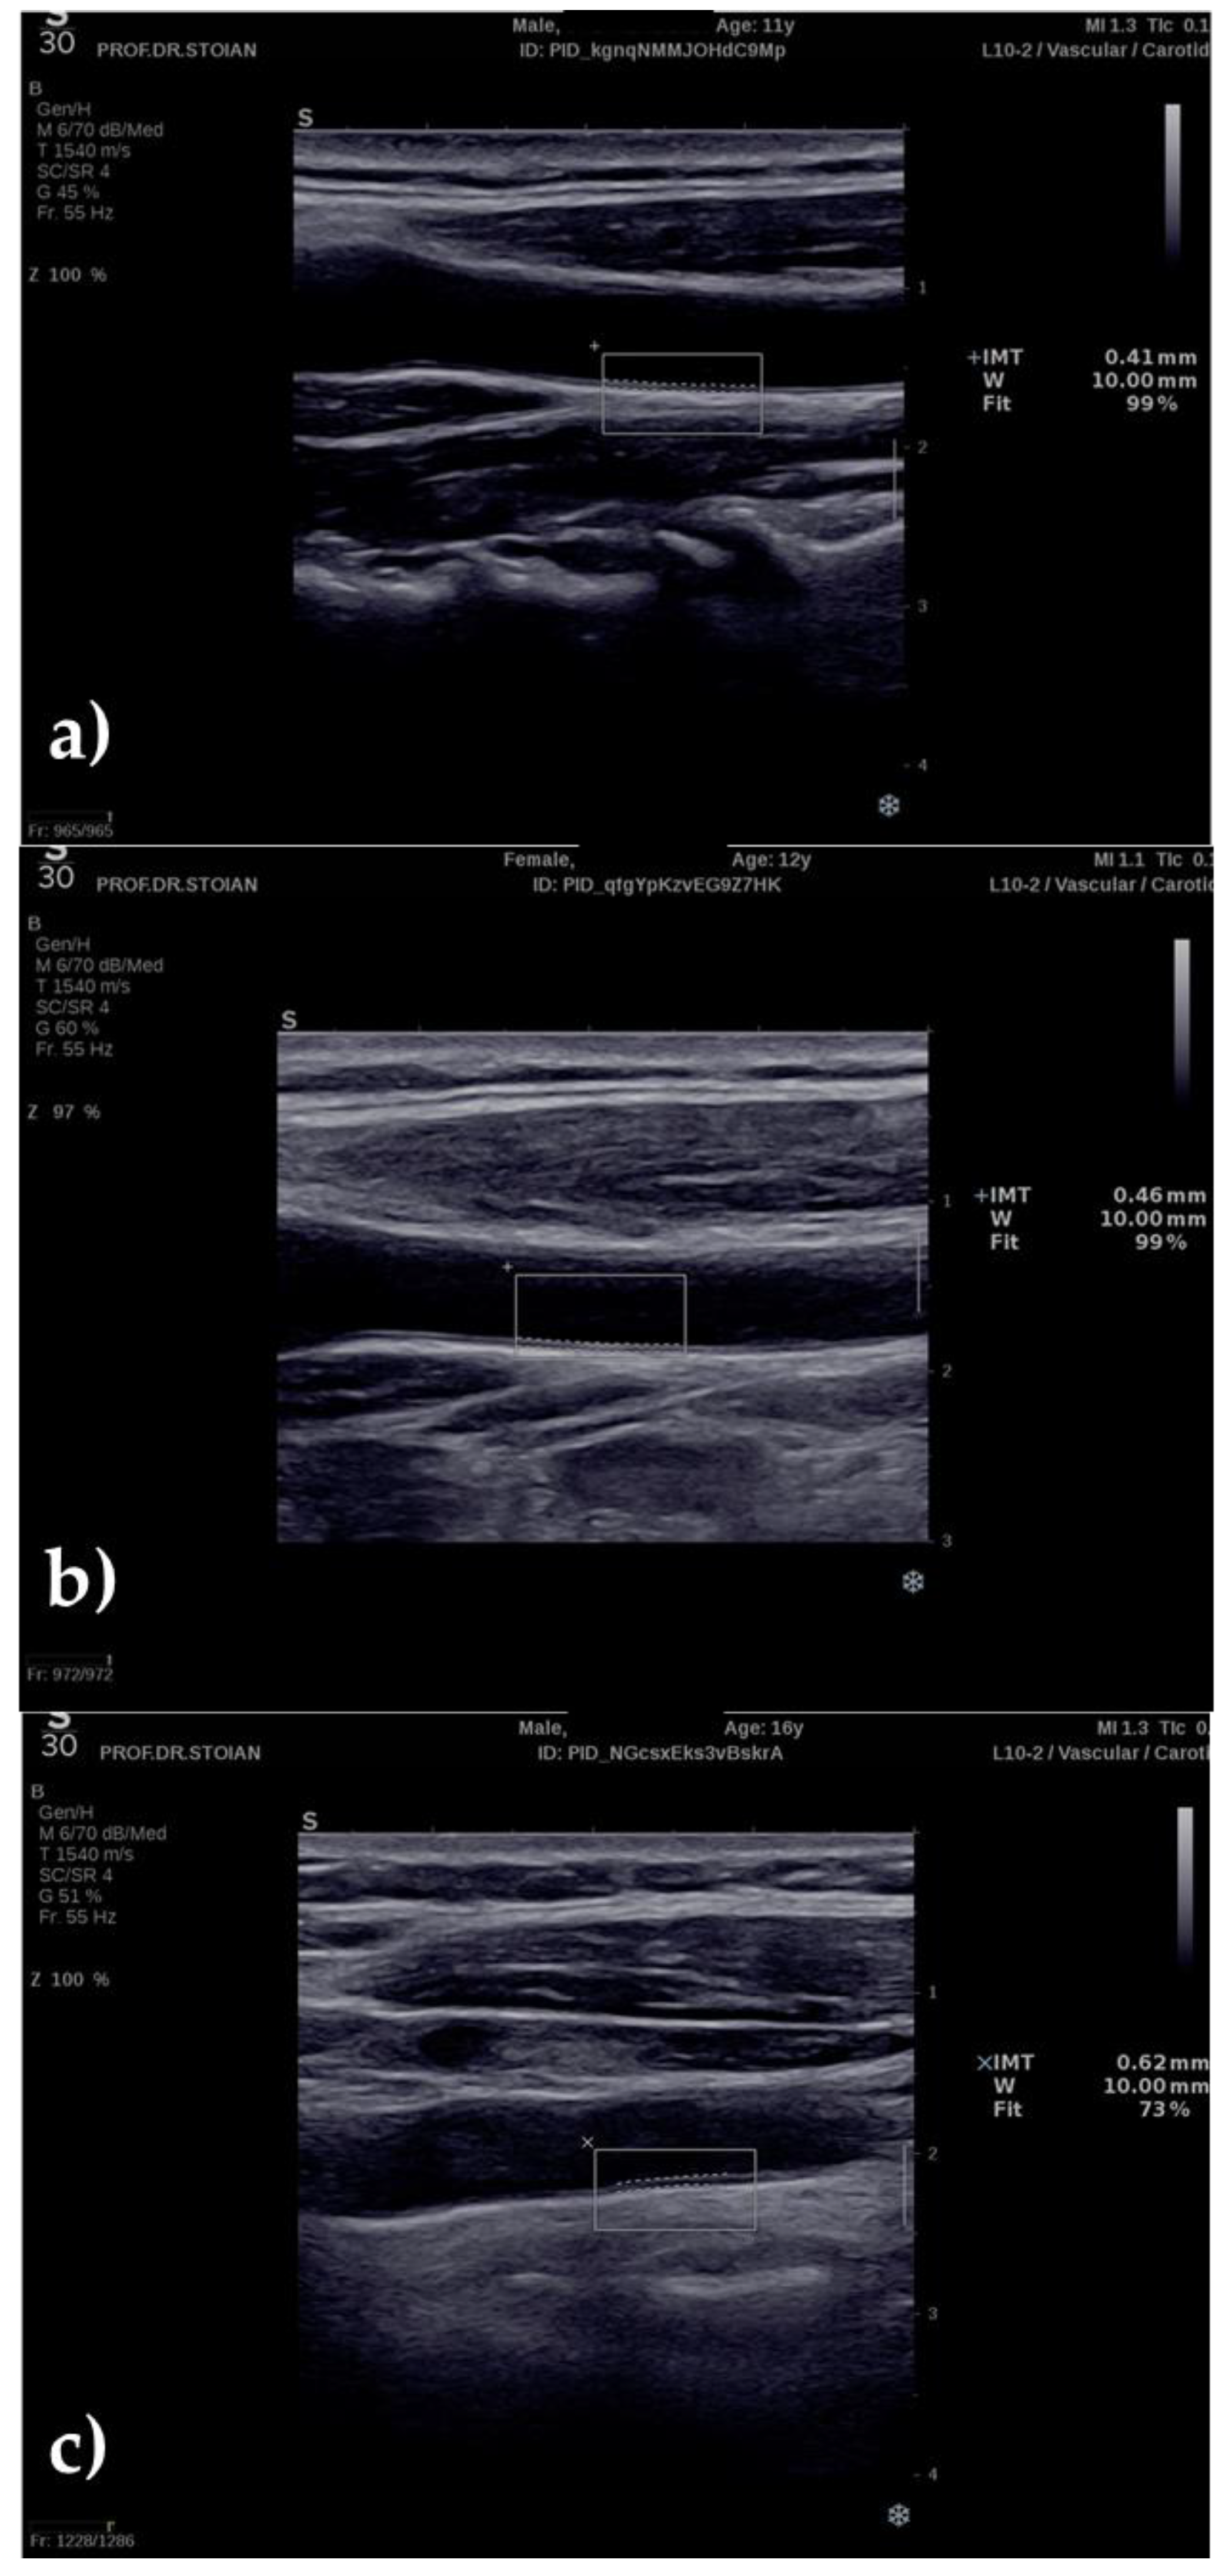

2.3. Ultrasonography Technique